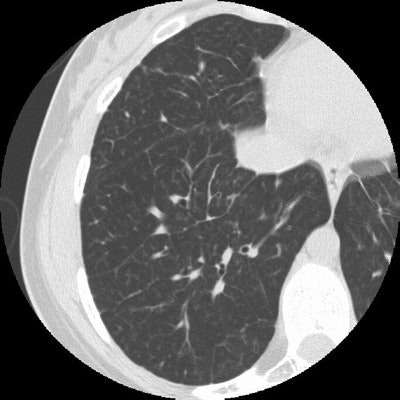

Sarcoid Stage 4:

The case below in from a patient with a history of sarcoid. The HRCT examination demonstrates interstitial lung disease with peripheral traction bronchiectasis that has been stable over the past several years. (Click image to enlarge)